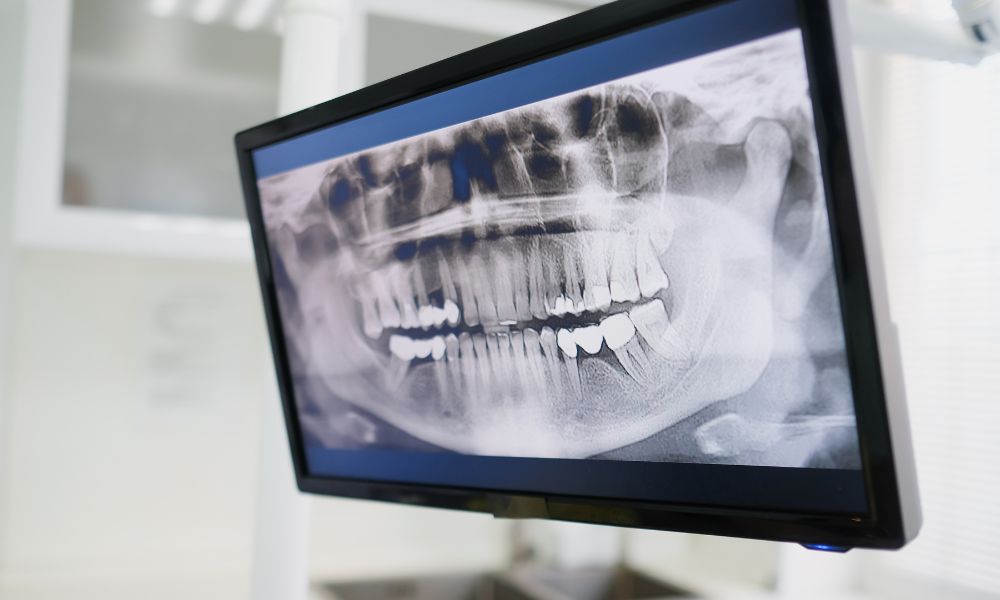

Khách hàng được chụp ảnh trong miệng, ảnh góc mặt kết hợp với phim X-quang, CT chuyên dụng. Dựa trên các dữ liệu này, mức độ sai lệch răng được phân tích chính xác, làm cơ sở xây dựng phác đồ chỉnh nha phù hợp và an toàn cho từng trường hợp niềng răng cố định mắc cài.